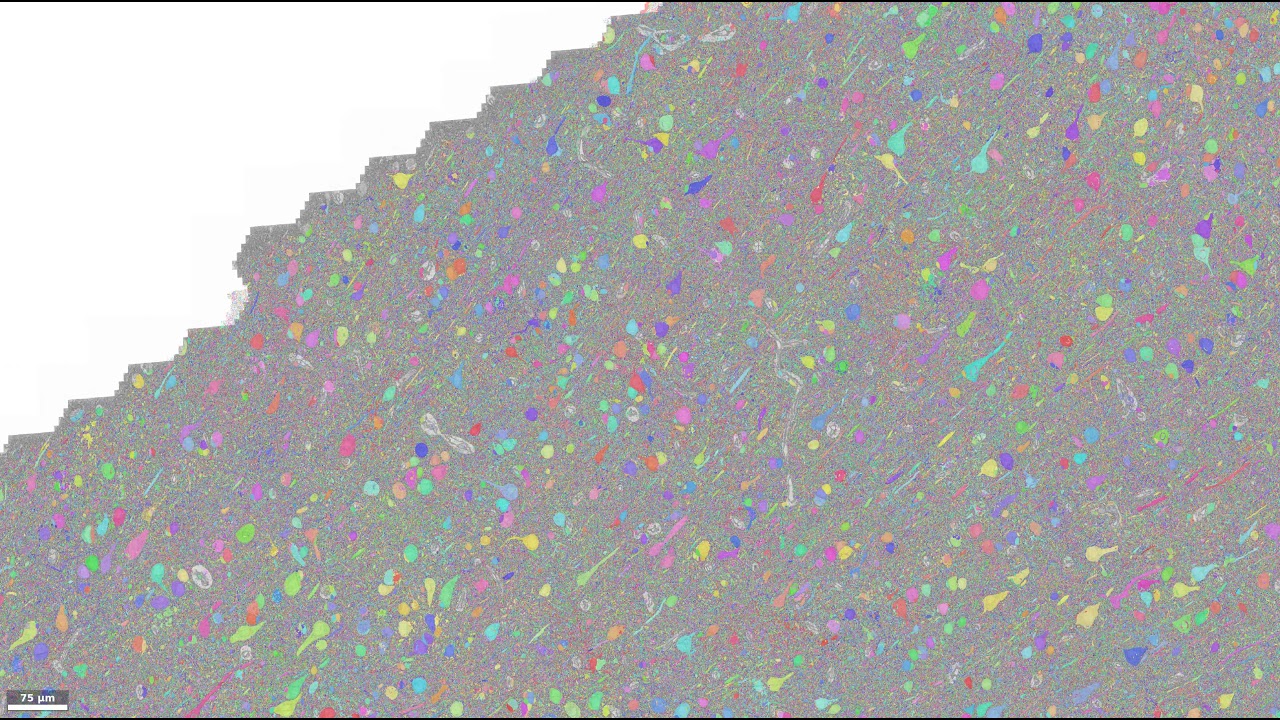

Вчені оцифрували мозок людини. Фото з відкритих джерел

Вчені з Гарвардської лабораторії Ліхтман спільно з компанією Google змогли оцифрувати 1 кубічний міліметр тканини кори головного мозку людини. Для цього, вчені взяли у хворого на епілепсію пацієнта частина мозку. Отримані зразки були розділені на 5 300 секцій, товщиною по 30 нанометрів кожен. Потім, кожен шар був просканований, а зображення передані в компанію Google.

Всього від вчених Google отримала 225 мільйонів зображень, з яких в компанії створили єдину 3D-модель частинки мозку, об'ємом в 1,4 петабайта.Вчені планують, що завдяки отриманій моделі мозку їм вдасться ретельно вивчити природу захворювань головного мозку людини на ранніх стадіях.

Для довідки: отримана 3D модель мозку розміром 1,4 петабайта є однієї мільйонної від обсягу всього людського мозку.